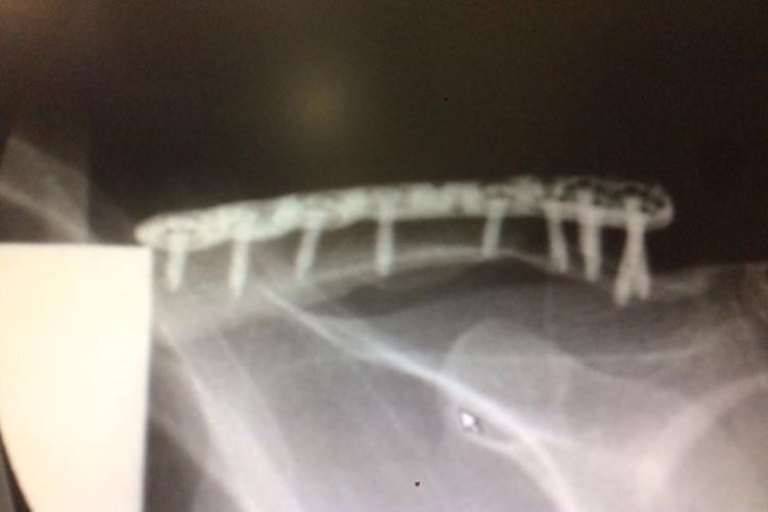

Gegenüber SPEEDWEEK.com schilderte der 29-Jährige den Crash und die Folgen: "Ich habe im Rennen eine Bremswelle falsch getroffen und ging schwer zu Boden. Ich hab sofort gemerkt, dass das Schlüsselbein gebrochen war. Am Montag bin ich dann sofort in Eisenberg operiert worden, hab jetzt wieder ein paar Stücke Metall mehr im Körper. Am Wochenende sollte ich wieder zu Hause sein, dann geht es in die Reha, damit ich so schnell wie möglich wieder fit bin." "Ein gebrochenes Schlüsselbein drei Wochen vor dem ersten Meisterschafts-Rennen", seufzte Neugebauer. "Das hatte ich mir anders vorgestellt, aber wie man sagt: Verletzungen sind einfach Teil vom Motocross. Trotzdem ist noch nichts verloren!"